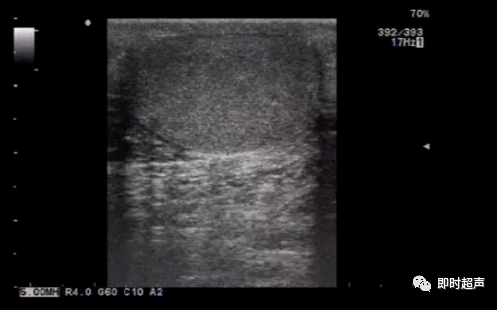

超声表现:

(1)位于皮肤层;

(2)形态规则,呈圆形或椭圆形;

(3)内部可为无回声,也可为均匀细点状回声。